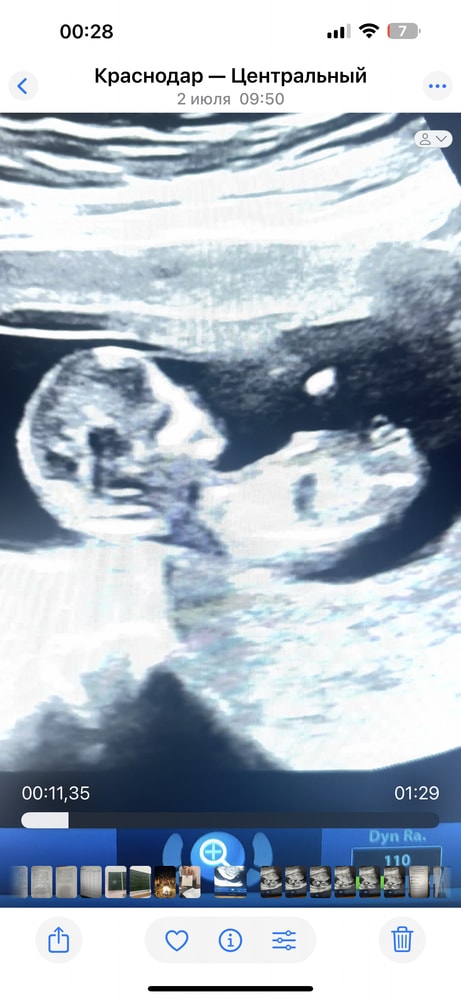

Похоже на мальчика у вас

Вот наш снимок на первом скрининге- мальчик оказался, подтвердили ив 15 недель